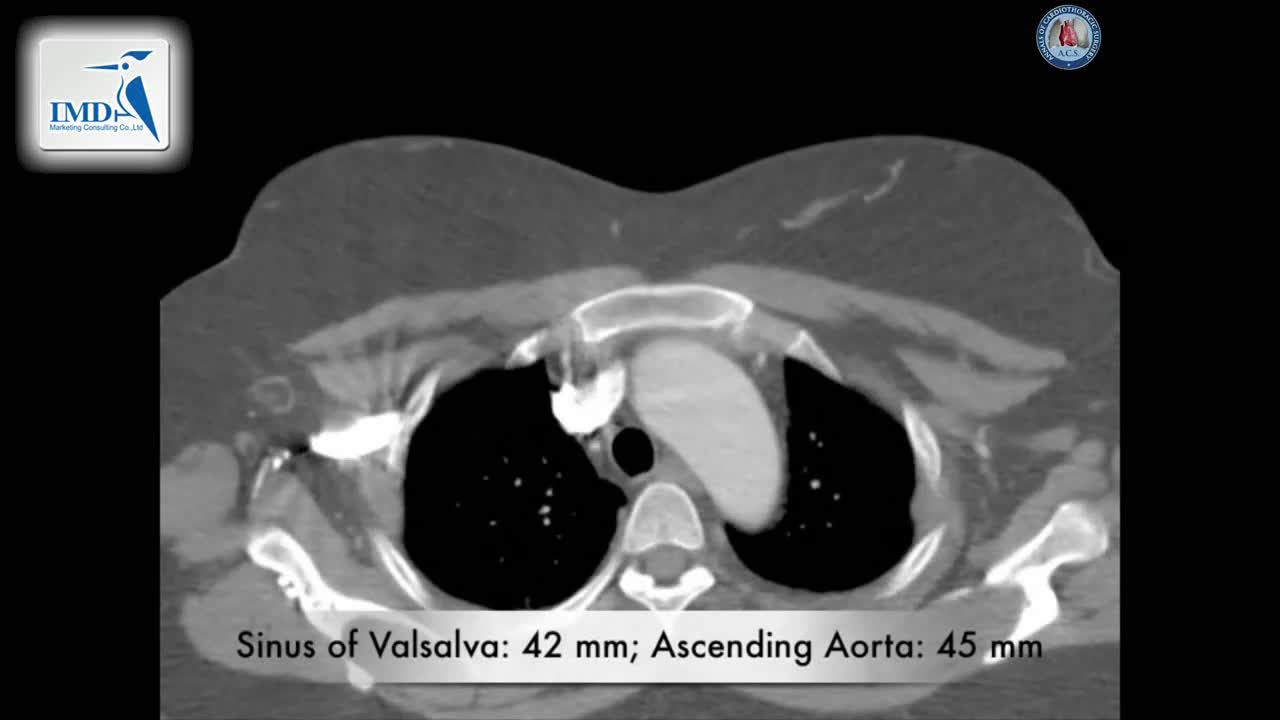

Bentall(复合带瓣管道)手术